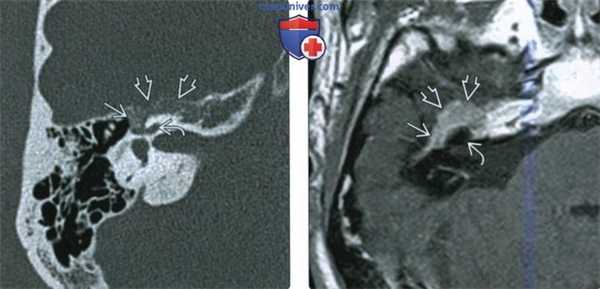

(Слева) На рисунке в аксиальной плоскости показана крупная шваннома лицевого нерва (ШЛН), состоящая из компонентов ММУ («мороженое») и ВСК («рожок»), напоминающая вестибулярную шванному. Поражение лабиринтного сегмента лицевого нерва позволяет сделать заключение.

(Справа) При аксиальной MPT T1 ВИ С+ FS у пациента с односторонней ней-росенсорной тугоухостью визуализируется ШЛН с компонентами ММУ и ВСК. Обратите внимание на «хвост» лабиринтного сегмента лицевого нерва, позволяющий отличить ШЛН от вестибулярной шванномы.